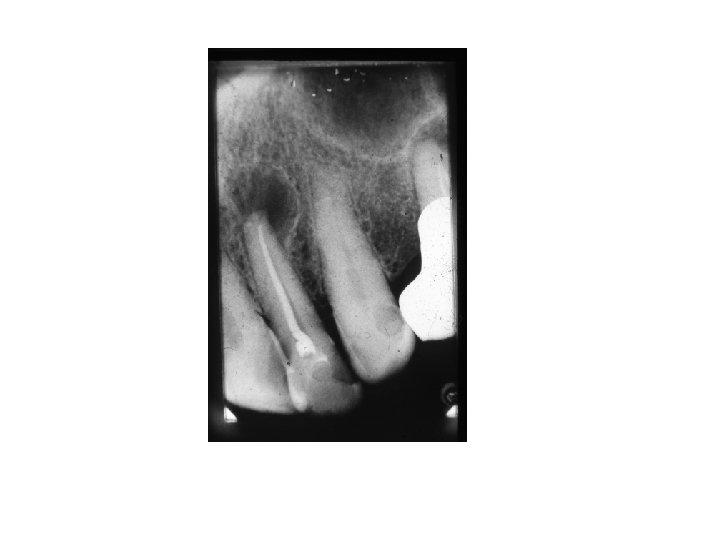

Pulpagangrena • 2 Typen: - Gangrena simplex- nur Pulpa ist tot, Röntgen- keine Veränderung. - Gangrena complex – Knochen im Umgebung der Wurzel ist auch tot. Es kann in 2 Variazion erscheinen: Ostitis rareficiens- Knochenverdünnung Ostitis slcerotisans- Knochenneubildung